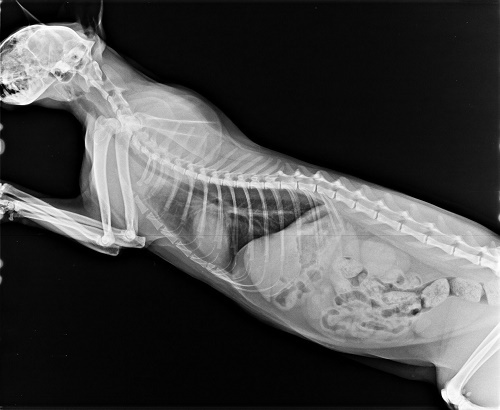

但可能之前在外流浪的食物不好,也沒有喝足夠的水,導致小葵口炎嚴重,牙齒一顆顆爛光,曾遭受重傷的她,個性緊張,無法刷牙,牙齦炎嚴重到口水一直分泌,她不小心吸入肺部,導致呼吸聲很大,怕拖下去越來越惡化,所以醫生在檢查過後,安排住院,先評估血檢、X光的情況,再給予洗牙、拔牙治療,拔了8顆爛牙後,小葵已出院,每天需噴一次口樂和拿賽可得,情況已獲得控制,只要半年洗牙一次就可以,她的住院費用,還需要大家的幫忙,讓這個小女孩的牙齒,可以保住,讓曾經飽受摧殘的她,能夠好好的吃一頓飯。